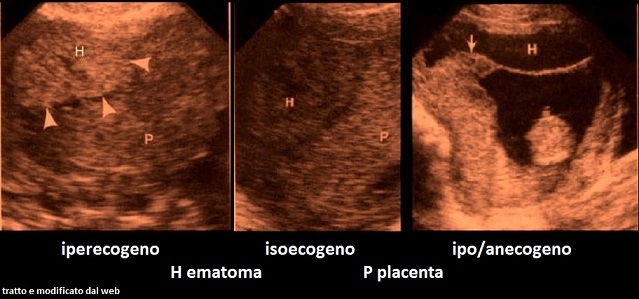

L'aspetto ecografico dell'emorragia retroplacentare varia in rapporto alla localizzazione ed al tempo di comparsa del sanguinamento. Nella fase iniziale l'emorragia si presenta ad aspetto iperecogeno, diviene isoecogena dopo 3-7 giorni e quindi ipoecogena dopo 1-2 settimane; inoltre gli ematomi, col passare del tempo, tendono a diventare più piccoli.